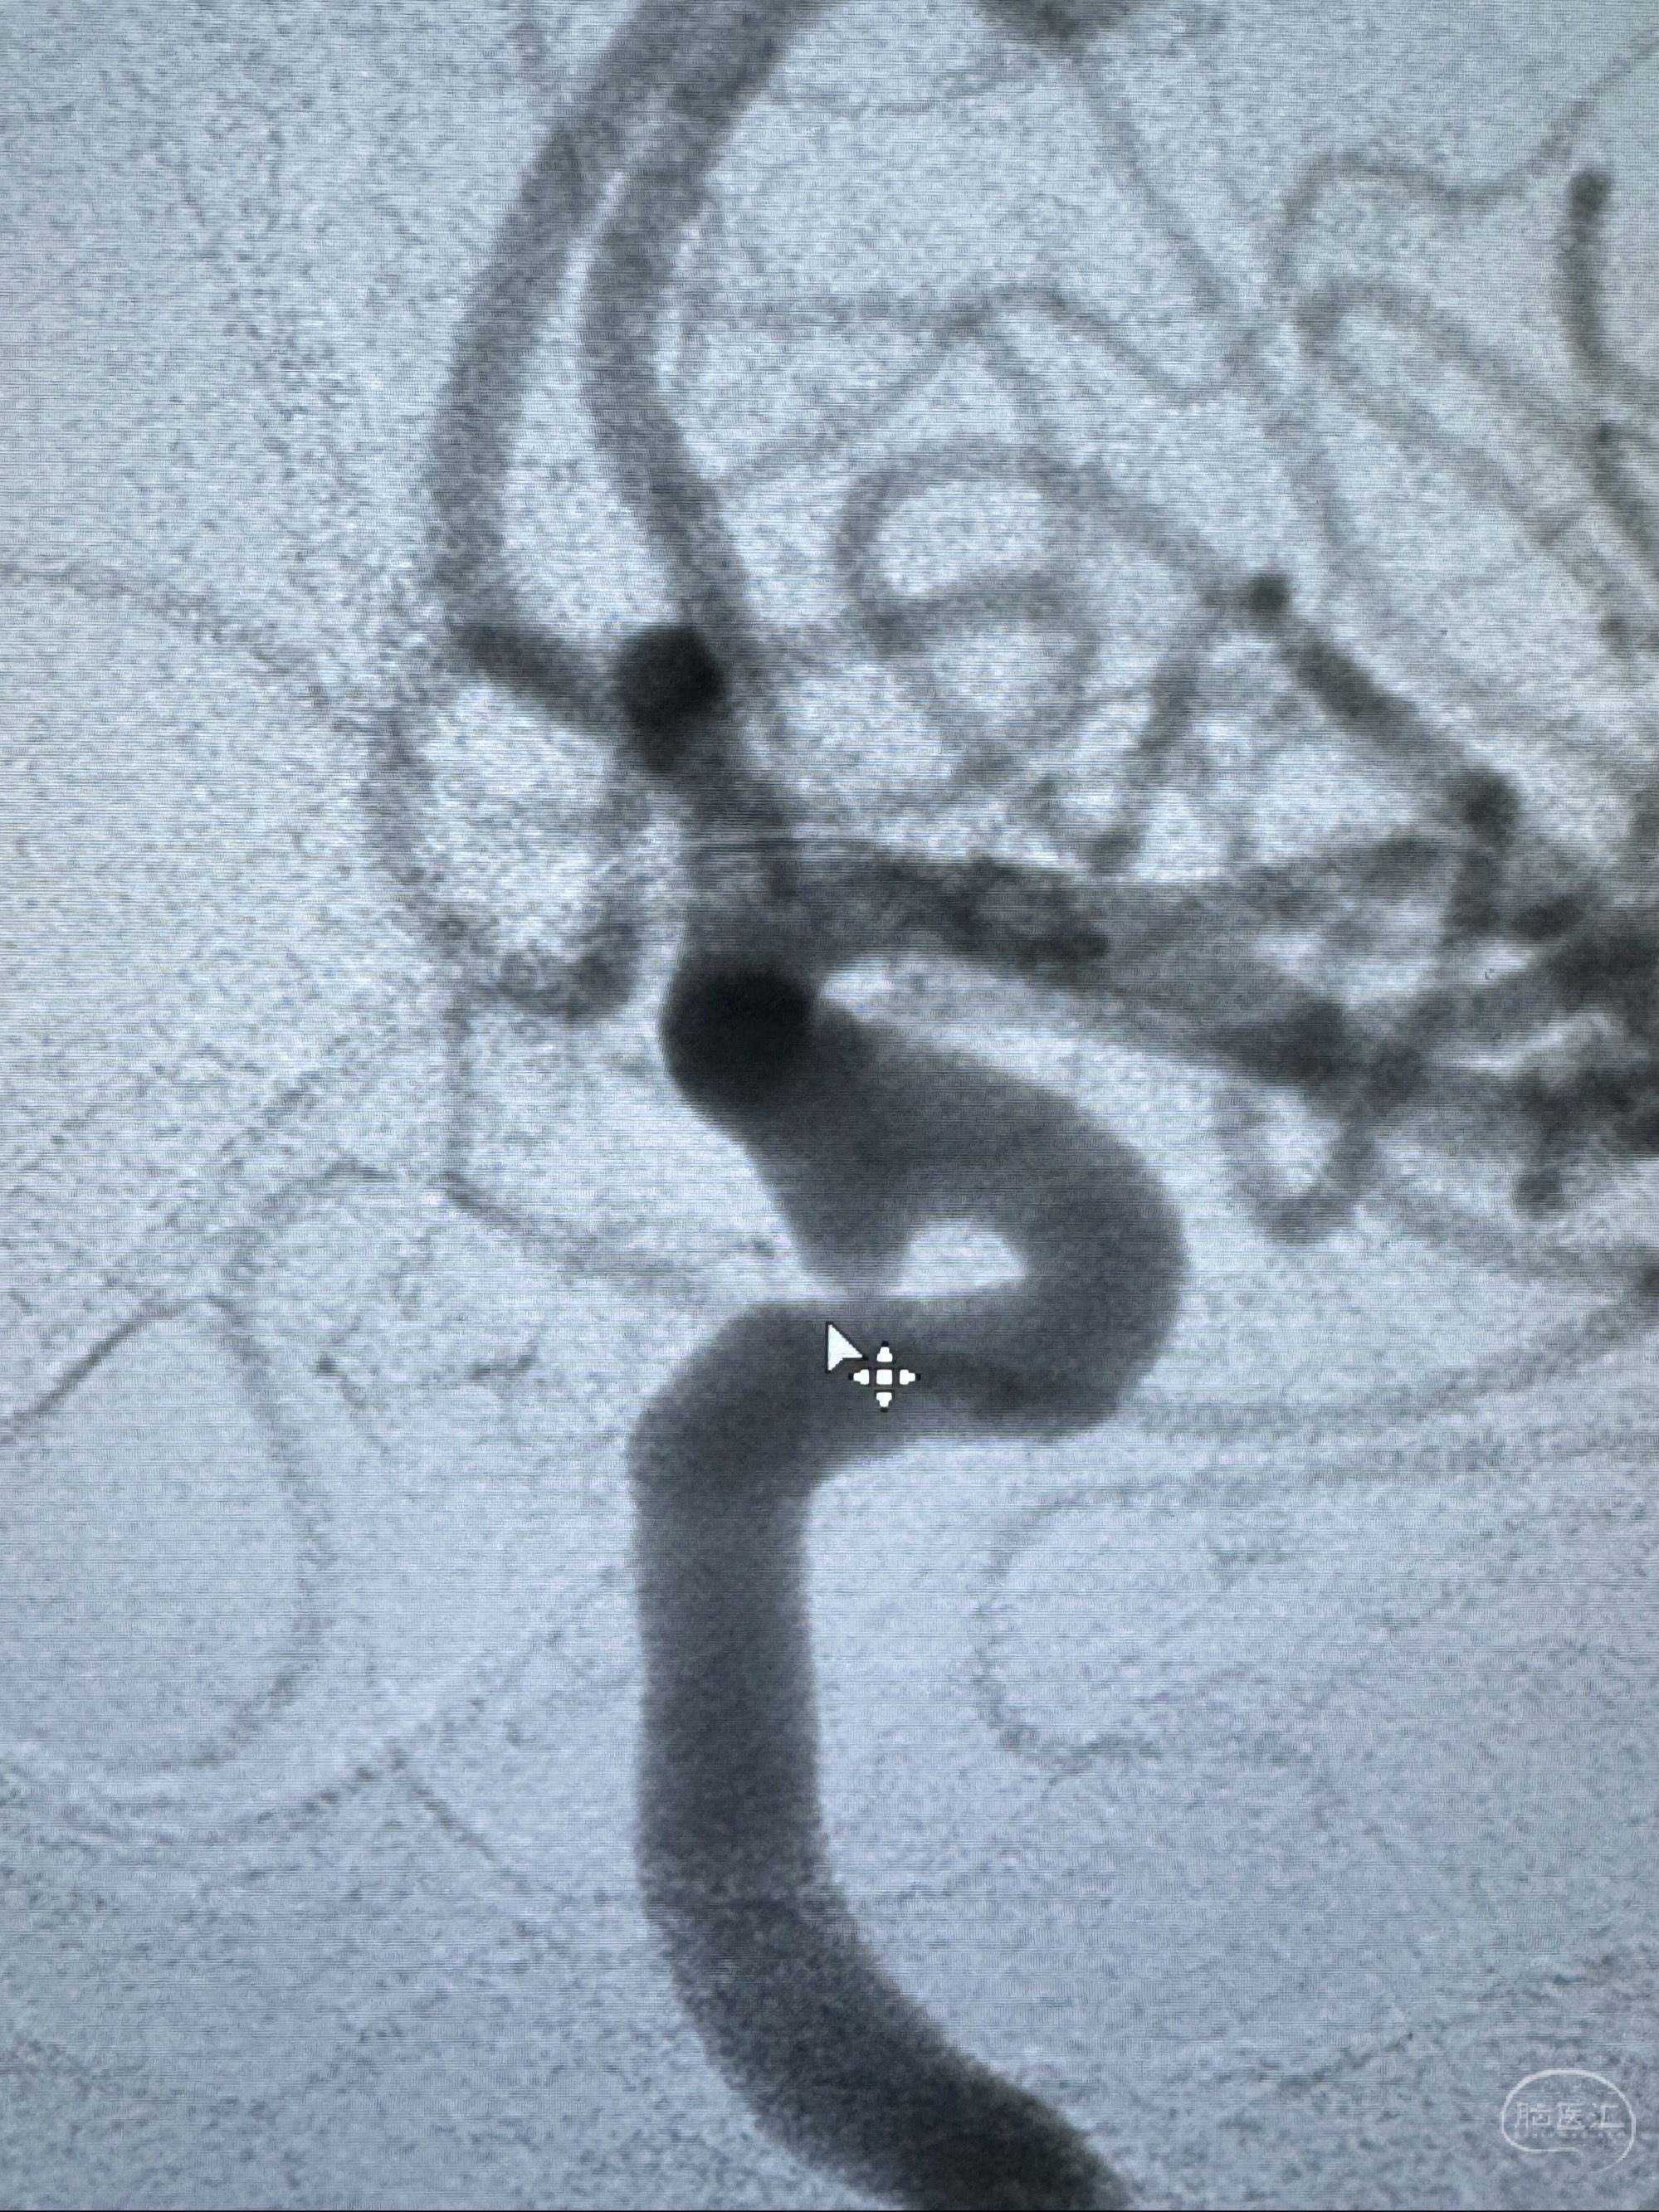

现病史:患者诉近4年来时有头痛发作,服用都梁软胶囊、氟桂利嗪对症治疗一月后症状改善,后头痛较少发作。近3月来患者头痛发作频率明显增加,约一月一次,为右侧偏头痛,胀痛,伴恶心呕吐,呕吐后症状可略减轻;遂于2023-11-01至蓝十字脑科医院就诊,查头颅MRI+DWI+MRA提示:左侧枕叶皮层下小斑片缺血或变性灶,右侧大脑前动脉A1段毛糙,显影淡、纤细,建议完善CTA;并于2023-11-03查头颅CTA提示:左侧颈内动脉C6段微小动脉瘤可能(约2mm),右侧大脑前动脉A1段纤细(对侧优势),左侧大脑中动脉提前分叉。现患者无明显不适,为求进一步诊疗颅内血管病变至我科就诊,收治入院。

2023-11-03 蓝十字脑科医院 头颅CTA:左侧颈内动脉C6段微小动脉瘤可能(约2mm),右侧大脑前动脉A1段纤细(对侧优势),左侧大脑中动脉提前分叉。

1.左侧颈内动脉瘤

治疗策略:

- 随访?

- 支架辅助治疗?